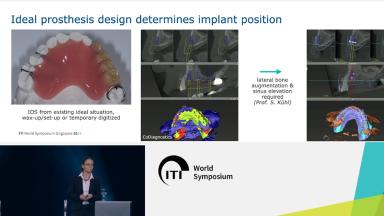

- plan and select suitable prosthetic abutment and emergence profile of the prosthesis

- plan the prosthetic design that will allow self-performed plaque control with ease